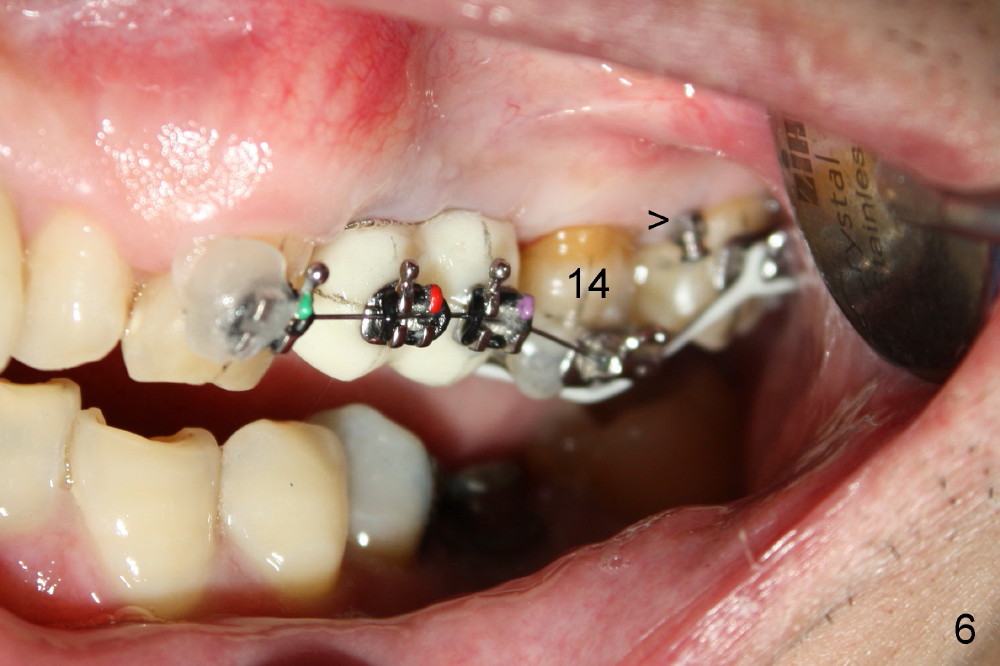

A 51-year-old man needs implants at the sites of #12,13,19 (Fig.1). The teeth #12 and 13 are extracted. An implant is placed at #19 (Fig.2 <). After osteointegration, an abutment is placed (Fig.2 A). The opposing tooth, #14, is found supraerupted. Two mini-implants are placed at the mesiobuccal and distolingual areas of #14 (Fig.3 (mirror view) <) and a power chain (*) is placed for intrusion. In the next 8 months, these 2 mini-implants become loose. Two new mini-implants are placed in the mesiolingual and distobuccal regions (Fig.4 ^). The one in the distobuccal region is loose after a while (Fig.6,7 >). In brief, mini-implants are not efficient in intrusion. At this time, the implants at the sites of #12,13 apparently osteointegrate (3 months post placement) and abutments are placed (Fig.4). Provisional crowns are fabricated (Fig.5). Brackets are placed between #11 and 15 with the bracket at #14 placed more coronally than those of the neighboring teeth (Fig.6-8). Mesially there are two excellent anchorages (#12,13) as well as the mesiolingual mini-implant. The distal anchorage is #15. In the next 5.5 months, the tooth #14 is intruded (Fig.9,10), but the 2nd molar is mobile (not as strong as #14). A longer mini-implant is placed in the distobuccal corner (>, more apical than before (Fig.7)). The distobuccal mini-implant is found to be mobile in 3 weeks (Fig.11). It appears that there is enough clearance for restoration of #19 (Fig.12). Power chains are placed between the mesiolingual mini-implant and #14 buccal tube until the appointment for crown prep. In this way, the lingual cusps may ascend (Fig.13 red arrow), while the buccal ones may descend (black arrow). The occlusal clearance will be more favorable.